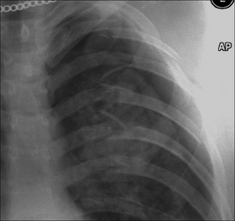

Following violent trauma the CXR is obtained with the patient lying on a trolley or examination couch. A large pneumothorax will be obvious. Smaller pneumothoraces are more difficult to detect on a supine CXR. Recognising a small pneumothorax is important—particularly if the patient is to be treated with positive pressure ventilation.

Figure 32.8 Pneumothorax. When the injured patient is lying supine, air in the pleural space collects at the highest point—i.e. anteriorly (a). On the frontal CXR the visceral pleural line may not be evident. The diagnosis will need to be made by scrutinising the areas around the dome of the diaphragm and adjacent to the lateral border of the heart (b). The black line outlining the diaphragm indicates a pneumothorax: see p. 97 for a detailed description.